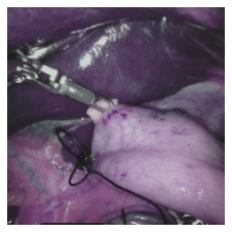

Endoscopic video recordings are widely used in minimally invasive robot-assisted surgery, but when the endoscope is outside the patient's body, it can capture irrelevant segments that may contain sensitive information. To address this, we propose a framework that accurately detects out-of-body frames in surgical videos by leveraging self-supervision with minimal data labels. We use a massive amount of unlabeled endoscopic images to learn meaningful representations in a self-supervised manner. Our approach, which involves pre-training on an auxiliary task and fine-tuning with limited supervision, outperforms previous methods for detecting out-of-body frames in surgical videos captured from da Vinci X and Xi surgical systems. The average F1 scores range from 96.00 to 98.02. Remarkably, using only 5% of the training labels, our approach still maintains an average F1 score performance above 97, outperforming fully-supervised methods with 95% fewer labels. These results demonstrate the potential of our framework to facilitate the safe handling of surgical video recordings and enhance data privacy protection in minimally invasive surgery.